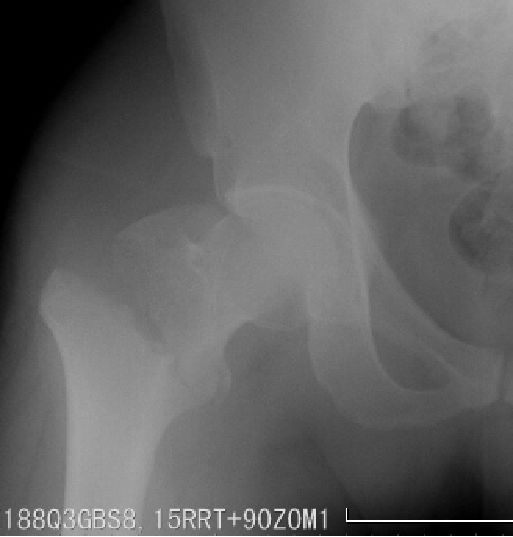

DHS(Dynamic Hip Screw)动力髋螺钉

以一根粗大宽螺纹的拉力螺钉与套管钢板及加压螺钉连接。在复位及骨折愈合过程中可使两骨折端靠拢,产生静力加压作用。对于顺转子间骨折线骨折可获得动力加压作用。

-

稳定骨折,固定成功

不稳定骨折,固定失败

用于骨质疏松患者有一定螺钉切除率,尤其是当拉力螺钉位置偏上时;

因钢板位于负重力线外侧,固定力臂较大,不适用于逆转子骨折。